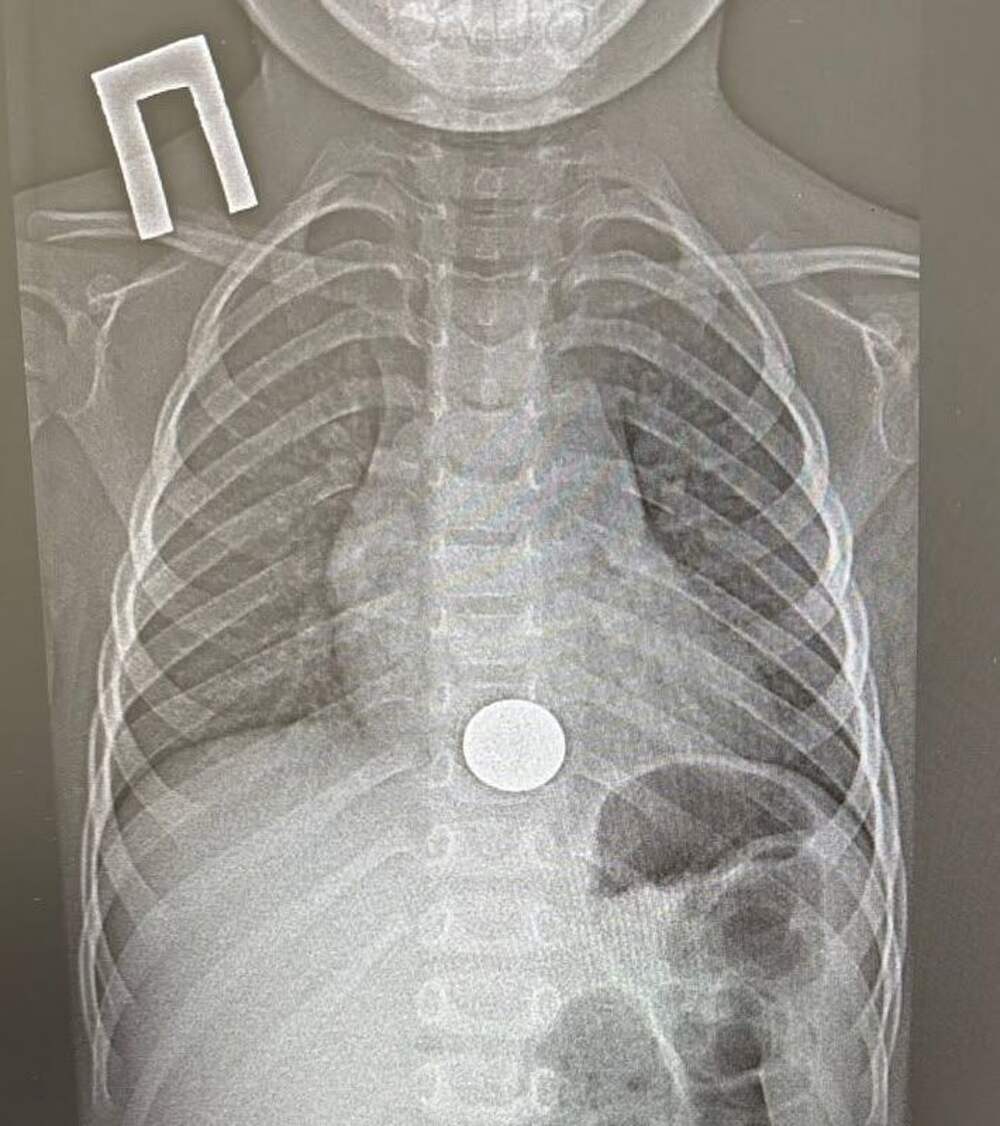

В Татарстане спасли двухлетнего ребенка, проглотившего монету

В Татарстане ребенок проглотил монету и попал в больницу. Об этом сообщает пресс-служба ГАУЗ НДРБ с ПЦ.

Инцидент произошел 15 декабря. Малолетний взял у старшего брата монету, чтобы поиграть с ней, и случайно ее проглотил. Ребенок сразу рассказал об этом родителям, и мать оперативно доставила его